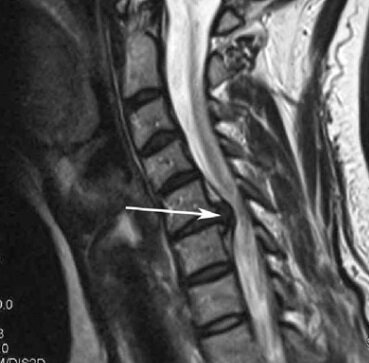

Как говорилось в начале статьи, чаще всего электрофорез применяют для лечения протрузии или грыжи межпозвоночного диска. Если по простому - это как "шишка" на колесе автомобиля, только в позвоночнике. Как это выглядит смотрите на картинках: